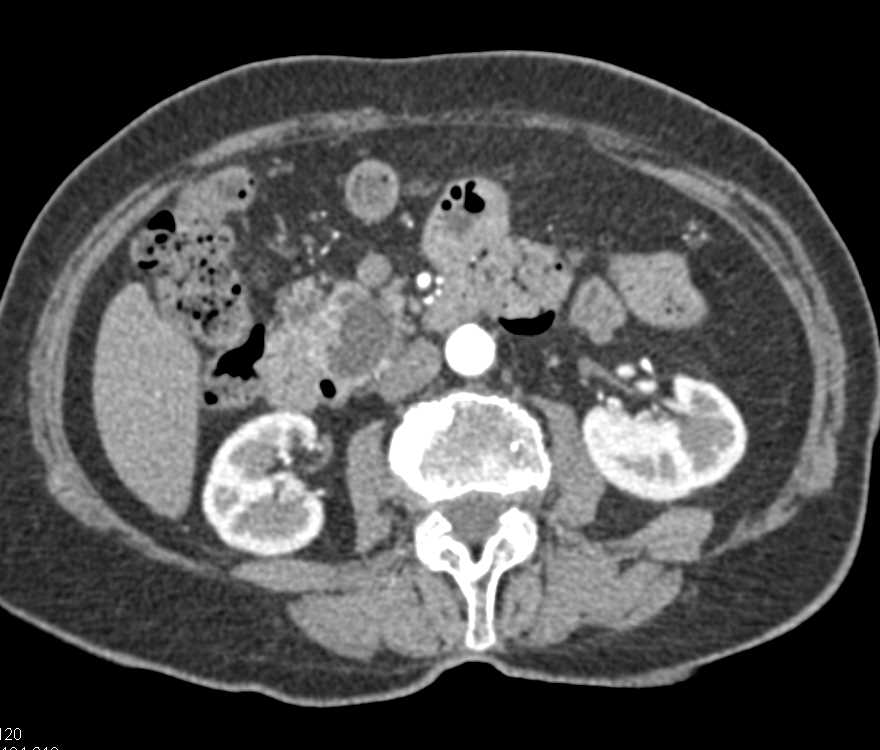

Pancreatic Cancer with Splenic Metastases